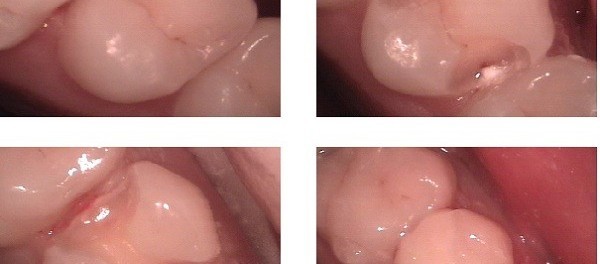

Dental surgery and related dental procedures are often feared to be painful experiences that can be avoided by attending to your dental needs. However dental surgery and related procedures are essential for : Maintaining the health and integrity of your teeth, gum and mouth. Restoring functioning of your teeth Preventing serious complications in the future. Improving the cosmetic appearance of the teeth and mouth. Understanding dental procedures often helps allay unrealistic fears surrounding dental surgery. Advances in pharmaceuticals, anesthesia, investigative and therapeutic techniques means that your dental procedure should be fairly painless and quick in the hands of a skilled dentist, periodontist or orthodontist. What is a tooth cavity? A tooth cavity is the destruction of the tooth structure due to lactic acid produced by bacteria in the mouth. Chipping and fractures of the tooth cause further damage to tooth structure. Cavities provide an ideal environment to trap food and allow bacteria to thrive while destroying greater portions of the tooth enamel (outer layer) and dentin (inner layer). Left unattended, the cavity will completely erode the tooth, cause a toothache or jaw pain or even complicate to form dental abscesses in the surrounding area. What is a tooth filling? A … Continue reading Dental Procedures & Surgery – Root Canal, Bridges, Implants